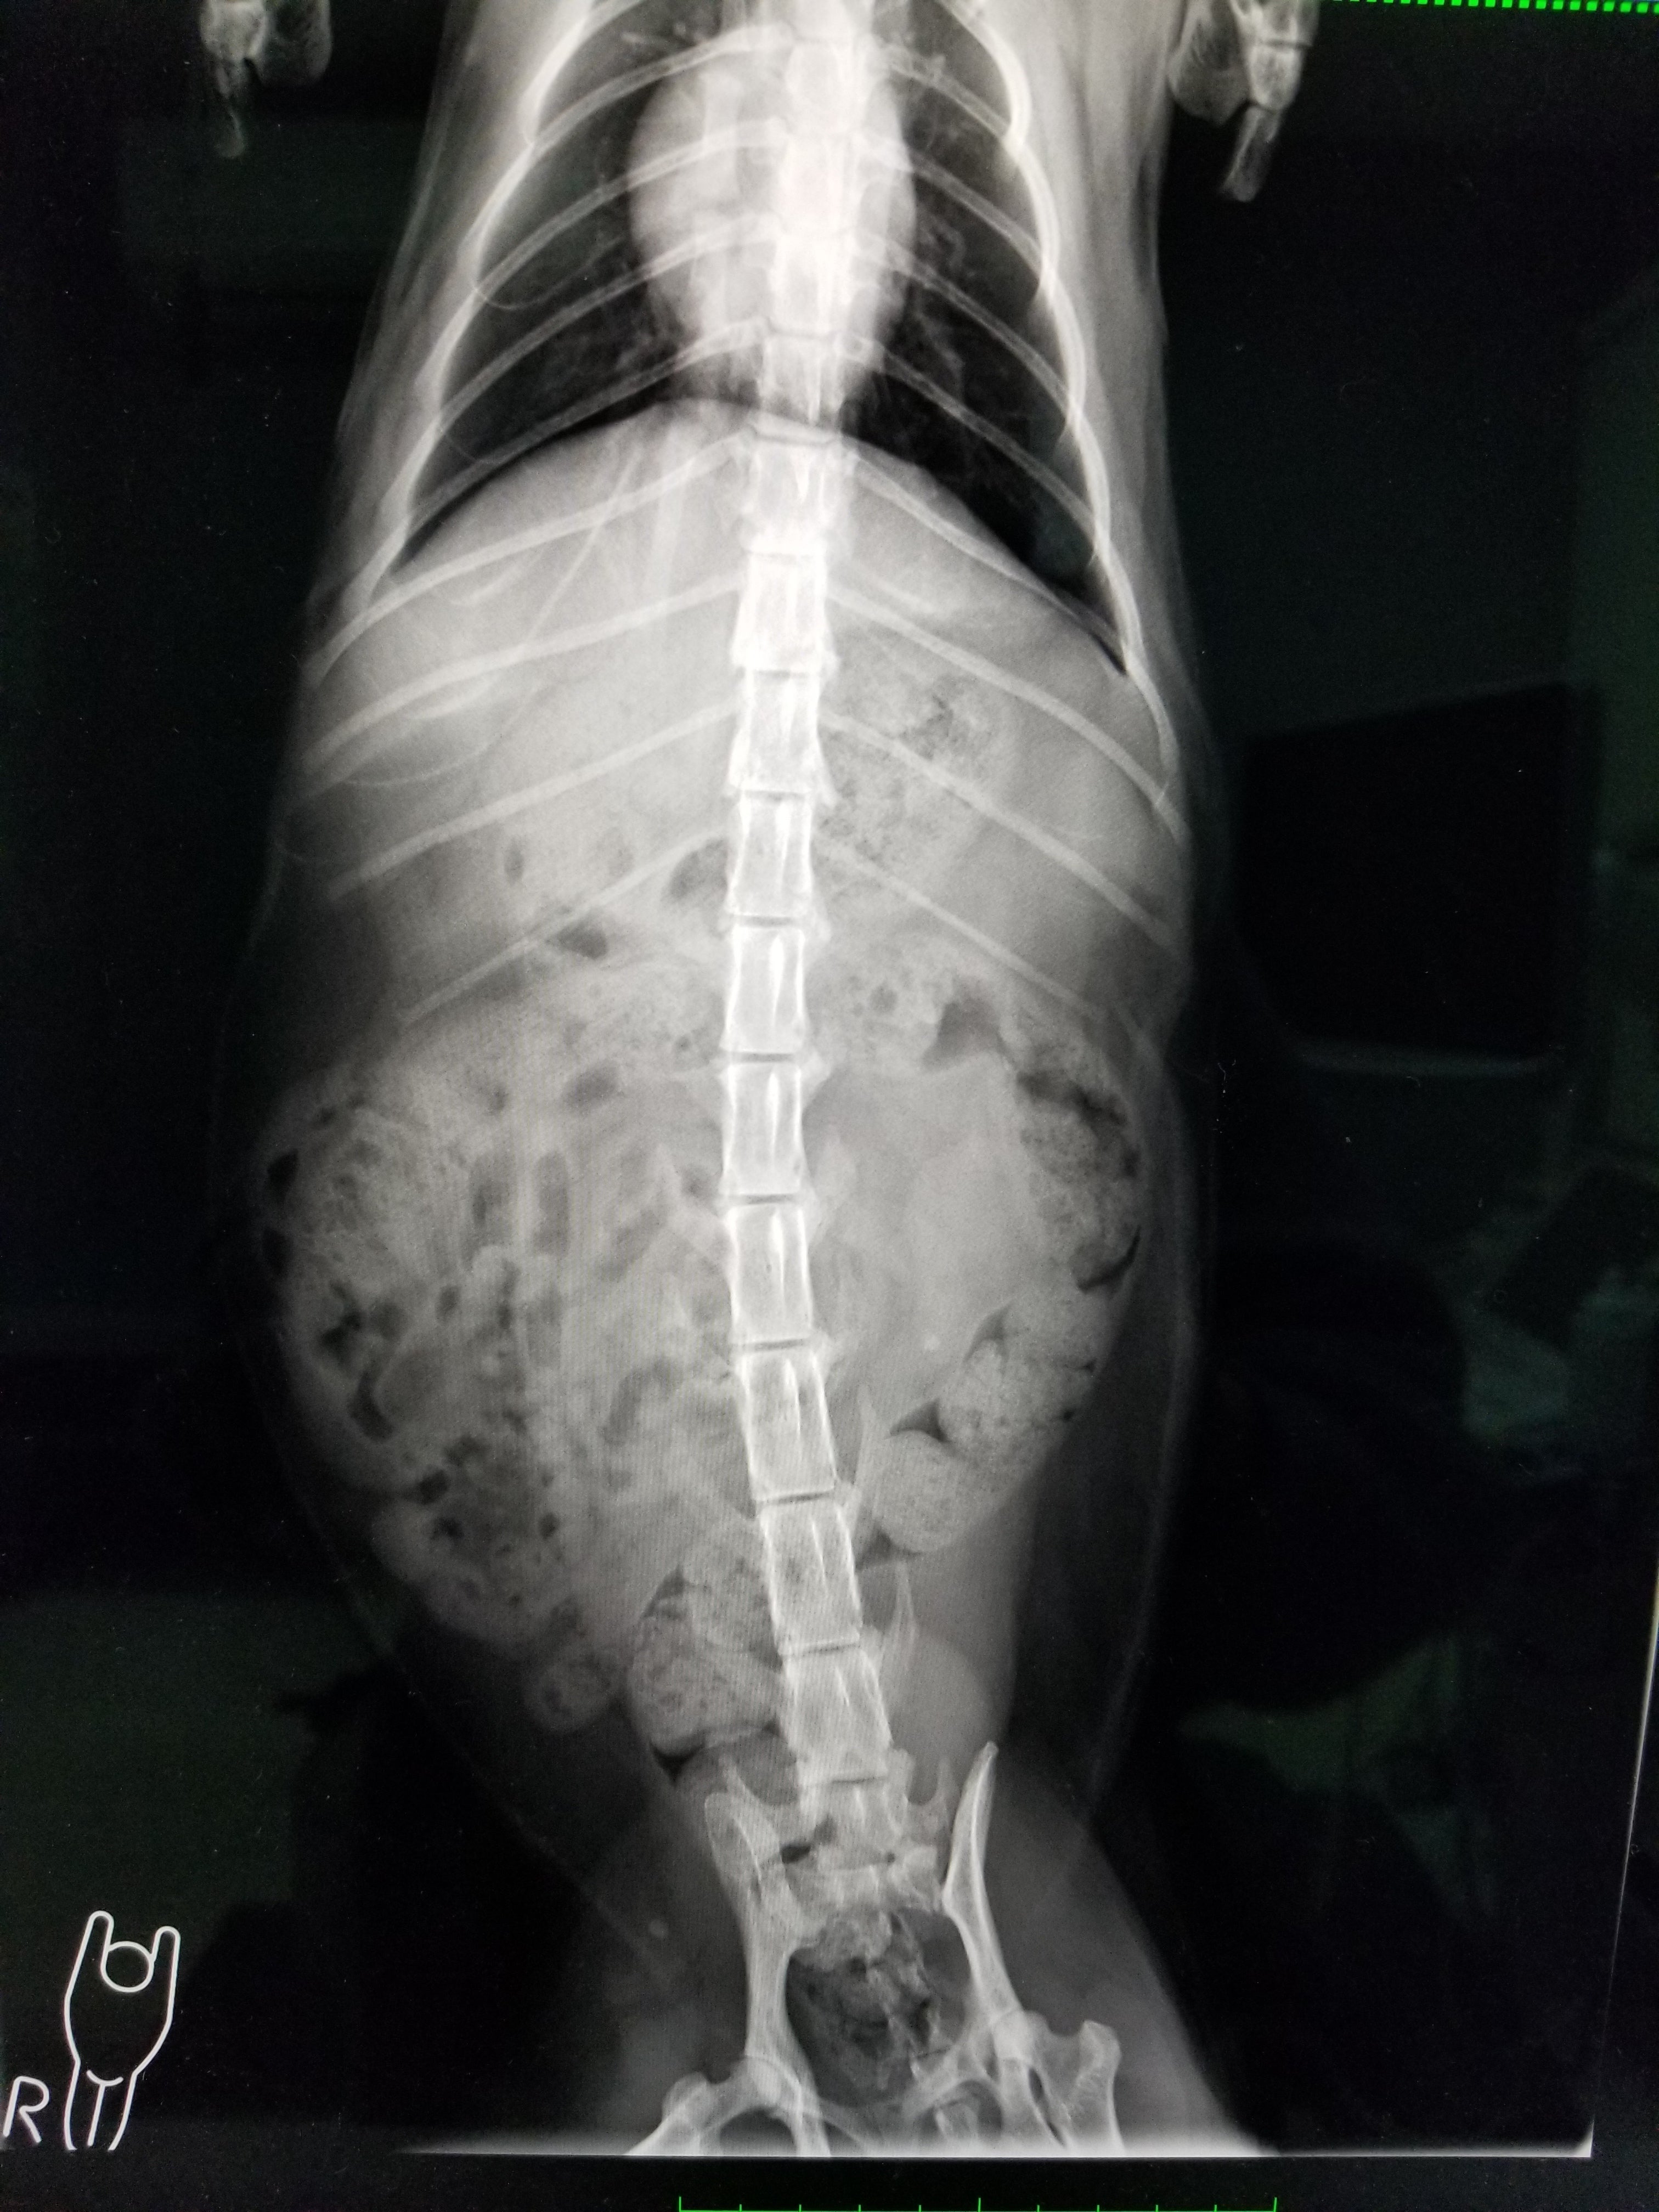

FIP(猫伝染性腹膜炎)です。発症から死に至ってしまうまでの期間は、最悪の場合、わずか平均9日間といわれ、年間で約1,000頭以上の猫ちゃんが苦しんでいると聞きました。

治すのには多額のお金が必要となり、飼い主さんからこれ以上はお金を出せないと相談されたため、保護しました。

現在も治療中で、感染症のため隔離されている状態です。